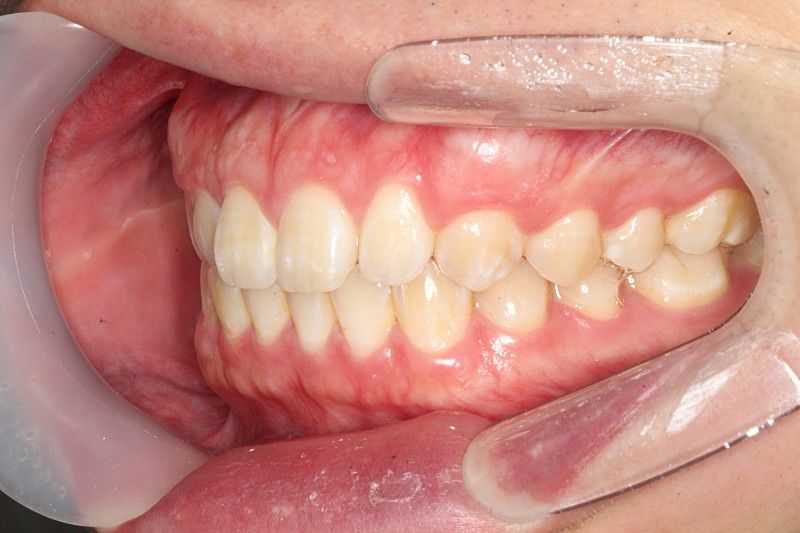

식사를 하거나 일상생활에서 교합을 하는데 큰 문제가 없다면 정상교합으로 판단합니다.

피개량이 적긴하지만 위에 치아가 아래 치아를 덮고 있다면 반대교합이나 절단교합이 아닌 정상교합의 범주에 있다고 판단을 하게 됩니다.